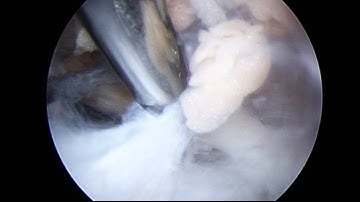

Suprascapular Nerve Decompression Case - Part 1